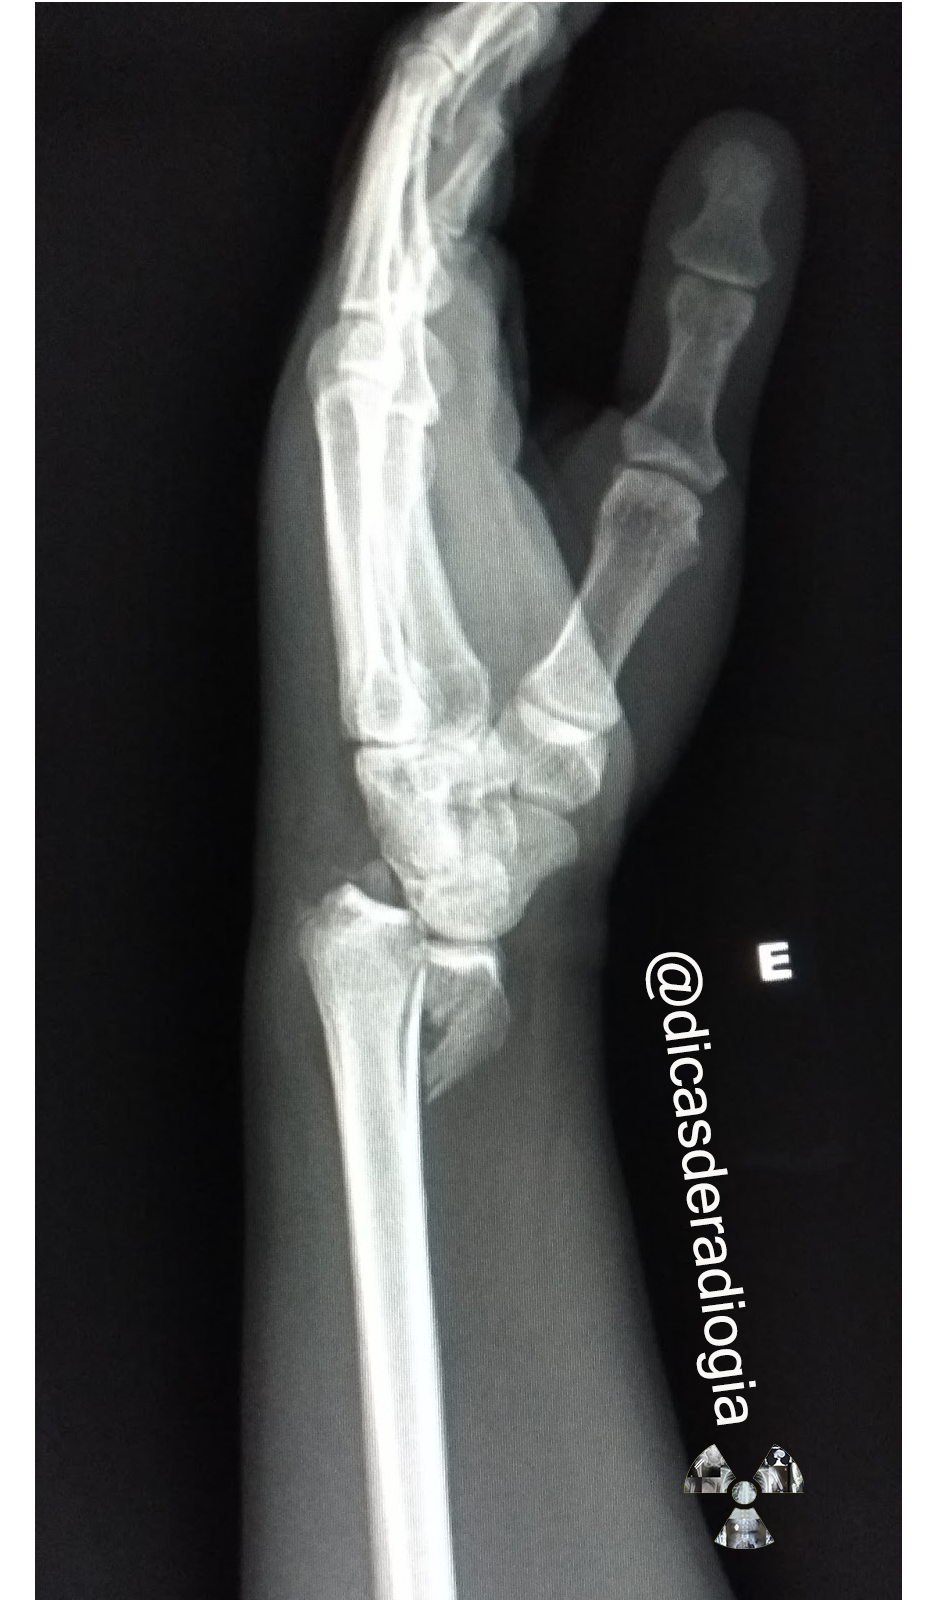

DICAS DE RADIOLOGIA Tudo Sobre Radiologia IMAGENS RADIOLÓGICAS FRATURA DO RÁDIO FRATURA

DICAS DE RADIOLOGIA IMAGENS RADIOLÓGICAS FRATURA DISTAL DO RÁDIO FRATURA DE COLLES